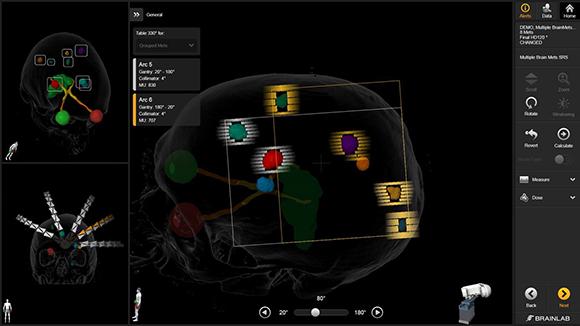

多発性脳転移SRS専用アプリケーション(Elements Multiple Brain Mets SRS)

Elements Multiple Brain Mets SRS は、複数の脳転移に対する定位放射線治療(SRS)の治療計画を効率的に作成するためのソフトウェアです。脳内に複数存在する転移性腫瘍に対して、それぞれの病変を正確に捉えながら放射線を集中させる治療計画を、自動化・最適化することができます。

本ソフトウェアでは、MRIやCT画像をもとに病変の位置や形状を解析し、複数の腫瘍に対して同時に高精度な照射計画を作成することが可能です。これにより、腫瘍には十分な線量を届けながら、周囲の正常脳組織への影響を可能な限り抑えた治療を目指します。

また、治療計画作成の効率化により、患者さんの治療準備にかかる時間の短縮にもつながります。このように、Elements Multiple Brain Mets SRS は、複数の脳転移に対して安全性と精度の高い定位放射線治療を実施するための治療計画支援システムです。